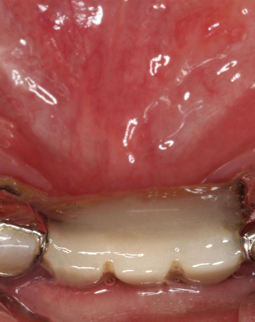

前几天回医院复诊检查和取模了发现我的种植体愈合挺好,今天过去准备把临时牙戴上,赶紧把这个空洞给补了,不然太尴尬了,戴牙冠之后医生给我把牙冠重新打磨了一下,说是要调整咬合,还要我模拟了下日常的咀嚼动作。哈哈哈,说件搞笑的事吧,我看见医生桌子上有个苹果,当即抓过来啃了一口,哈哈哈哈,这苹果太甜太好吃了,但医生还是建议我,先不要去吃硬物,等种植体再生长牢固一些,到时候想吃啥就吃啥。

到今天为止,我算是马上就有牙了。回想刚种牙那天,整个过程一点都没有痛觉,感觉自己就是在牙椅上睡了一觉,醒来后牙齿就长出来了,一切感觉是在做梦一样,非常棒的技术,戴上临时牙之后,可以正常的工作,也可以出席各类公开的活动,基本上解决了之前很多的麻烦,但还是不能吃太硬的东西,不太敢吃,医生跟我说“伤筋动骨一百天”,现在牙齿是戴上了,但是临时的,最主要是种植体还需要时间才能和我的牙床“相亲相爱”,接下来我就准备注意护理,让种植体早日和我的牙槽骨融为一体。